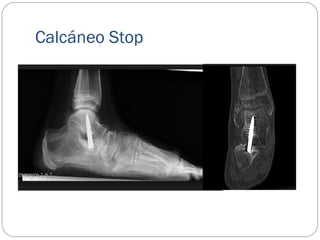

CALCANEO STOP

Se aborda el seno del 2 a 3 cm, exponiendo la faceta

subastragalina posteroexterna del calcáneo.

En su parte media y anterior se inserta un tornillo de

esponjosa, 4.0 mm. Mediante control rx.

Al atravesar las dos corticales quedara sobresaliendo unos 10

mm de la superficie superior del calcáneo, haciendo un tope

en el cuerpo del astrágalo.

Calcáneo Stop